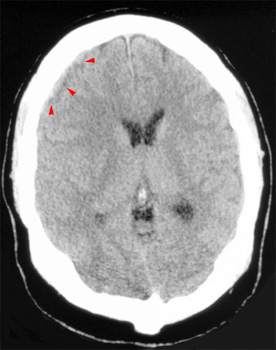

Question 7: Given the following head CT, the most likely diagnosis is: